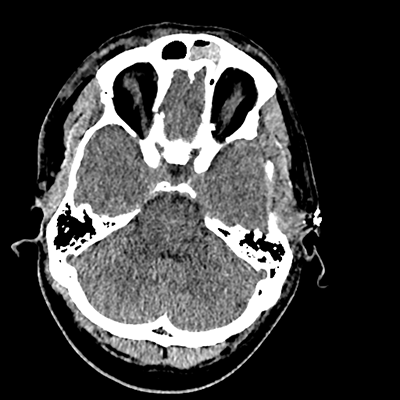

On day 5 of admission, he begins having intracranial hypertension again, spiking up to 40mmHg. You bolus with propofol and fentanyl, to no avail. You then push 30mL of 23.4% NaCl, which provides some brief improvement, allowing you to quickly get a non-contrast head CT. Unfortunately, he's now back up to 36mmHg. You review his labs, and note the following: Na 150, K 3.8, Cl 119, HCO3 18, BUN 21, Cr 0.85, glucose 136, sOsm 320.

NCHCT

NCHCT 7/20 7/20

NCHCT 8/20 8/20